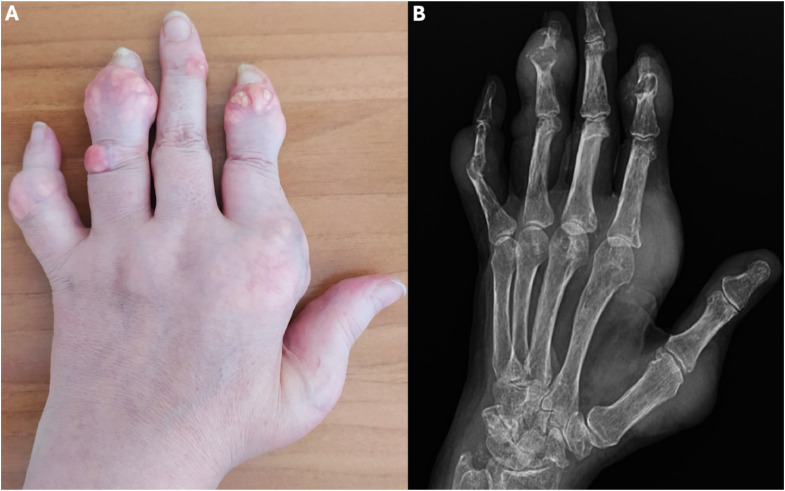

Gout is the commonest form of inflammatory arthritis. Flares are the commonest presentation of gout. Typically, gout flares present as acute monoarthritis, and most often affect the first metatarsophalangeal joint ('podagra'). Other joints in the lower limbs are affected more often than those in the upper limbs. Joint aspiration followed by examination of the synovial fluid using a polarised light microscope is the gold standard for a definite diagnosis of gout. Gout may be diagnosed without recourse to joint aspiration if there is podagra, elevated serum urate and no suspicion of infection. Ultrasonography and dual energy computed tomography may be used to diagnose gout if joint aspiration is unsuccessful or not feasible. Oral colchicine, NSAIDs and glucocorticoids have similar efficacy for controlling gout flare with differing adverse effect profiles. Consequently, the drug choice depends on comorbidities and patient preference.